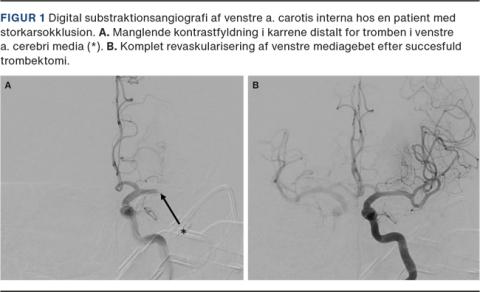

I forlængelse af de mange observationelle studier, der overordnet taler for en fordelagtig effekt af trombolyse, blev der gennemgået data fra den danske database, Dansk Apopleksi Register (DAP) [20]. Med afsæt i DAP blev der udført et retrospektivt studie, hvor man inkluderede patienter, der havde iskæmisk apopleksi og var behandlet med trombektomi med eller uden trombolyseforbehandling på Aarhus Universitetshospital i perioden 2015-2019 [21]. Baseret på administration af trombolyse blev patienterne inddelt i to behandlingsgrupper: En gruppe, der fik kombineret terapi med trombolyse og trombektomi, og en gruppe, der fik trombektomi alene. Det primære udfald var godt funktionelt udfald efter 90 dage defineret som modified Rankin Scale (mRS)-score 0-2 (selvhjulpen i daglige gøremål), og det sekundære udfald var succesfuld reperfusion defineret som modified thrombolysis in cerebral infarction scale (mTICI)-score 2b-3 (reperfusion af mere end halvdelen af det tidligere infarcerede område). I Figur 1 ses en patient, der havde M1-okklusion og efter trombektomi opnåede fuld reperfusion.

Patienterne i de to behandlingsgrupper adskilte sig ikke mht. alder eller apopleksiens sværhedsgrad, men der var en forsinkelse i ankomst til lyskepunktur på 8 min i gruppen, der fik kombineret terapi. Den statistiske sammenligning viste, at der var en signifikant højere andel af patienter med godt funktionelt udfald (57,1% vs. 38,8%, p < 0,0001) og succesfuld reperfusion (85,6% vs. 78,8%, p = 0,007) i gruppen, der fik kombineret terapi, end i gruppen, der fik trombektomi alene (Tabel 1). De patienter, der blev behandlet med kombineret terapi, klarede sig altså bedre end de patienter, der blev behandlet med trombektomi alene (Figur 2).